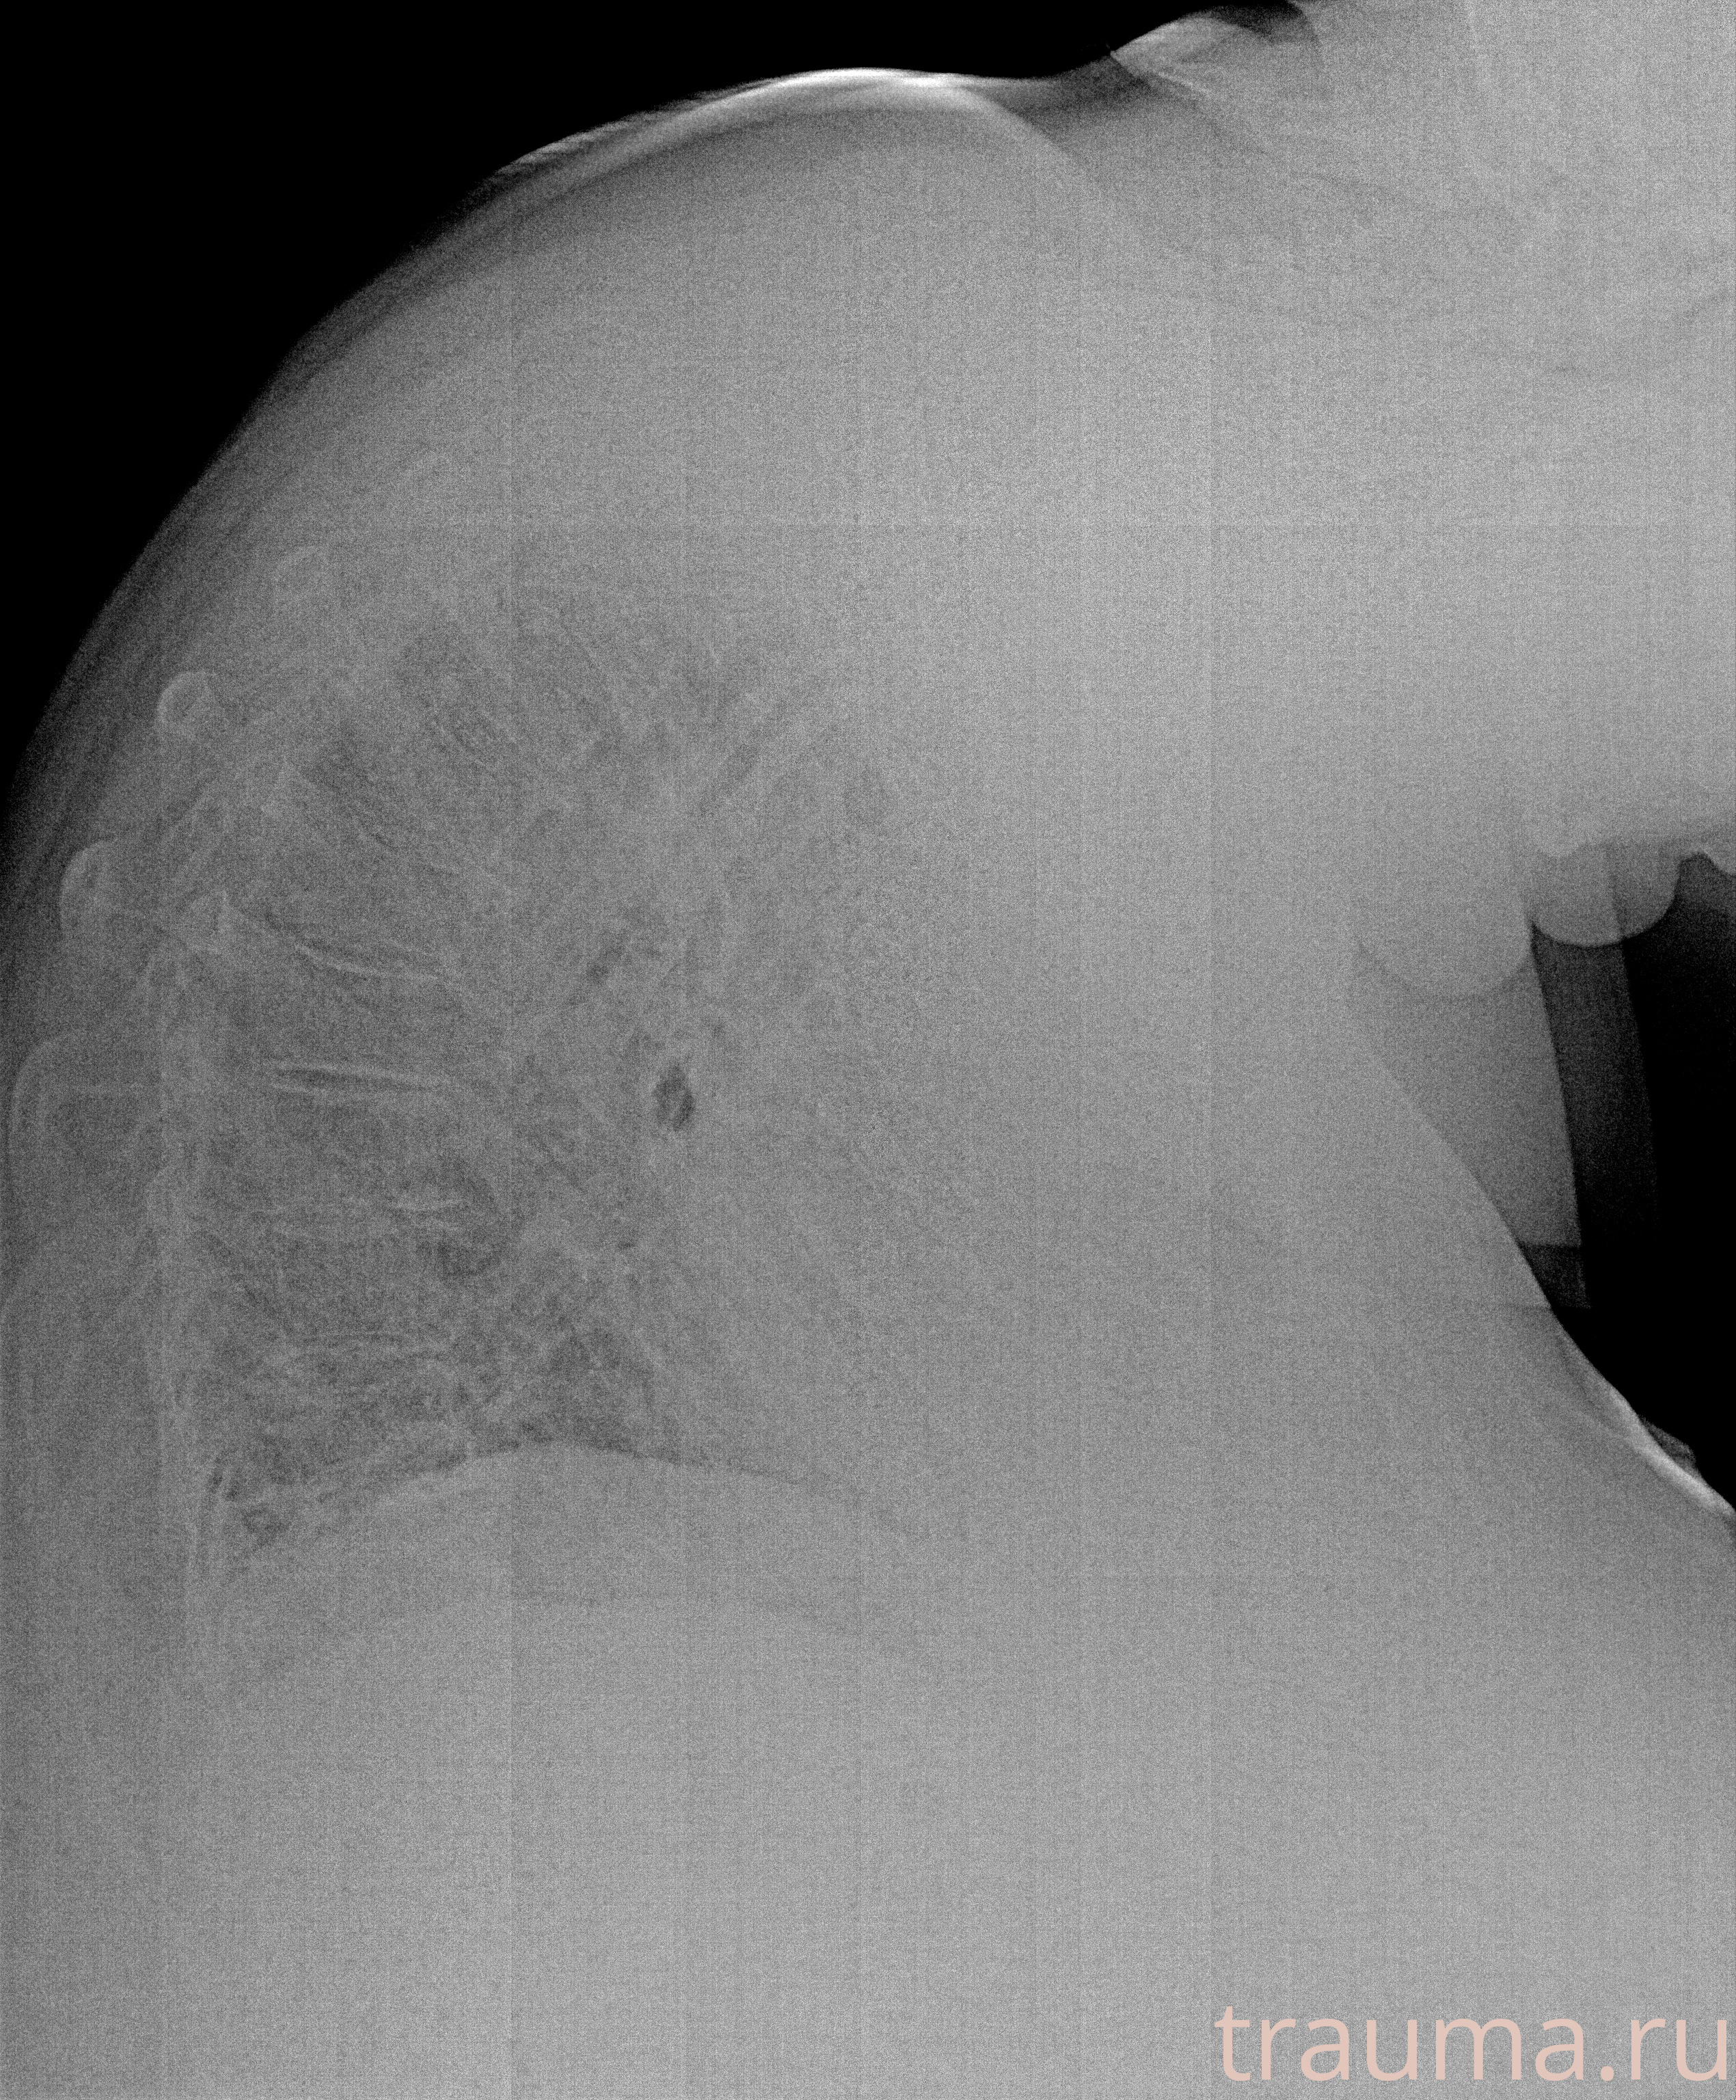

Рентген на дому: по вашему адресу приезжает врач-рентгенолог, травматолог-ортопед с мобильным рентгеновским аппаратом, проводит диагностику травмы или заболевания, делает необходимые рентгенограммы, дает рекомендации по дальнейшему лечению. Получить качественные снимки в домашних условиях возможно благодаря уникальной методике, разработанной МосРентген Центром для института  Склифосовского